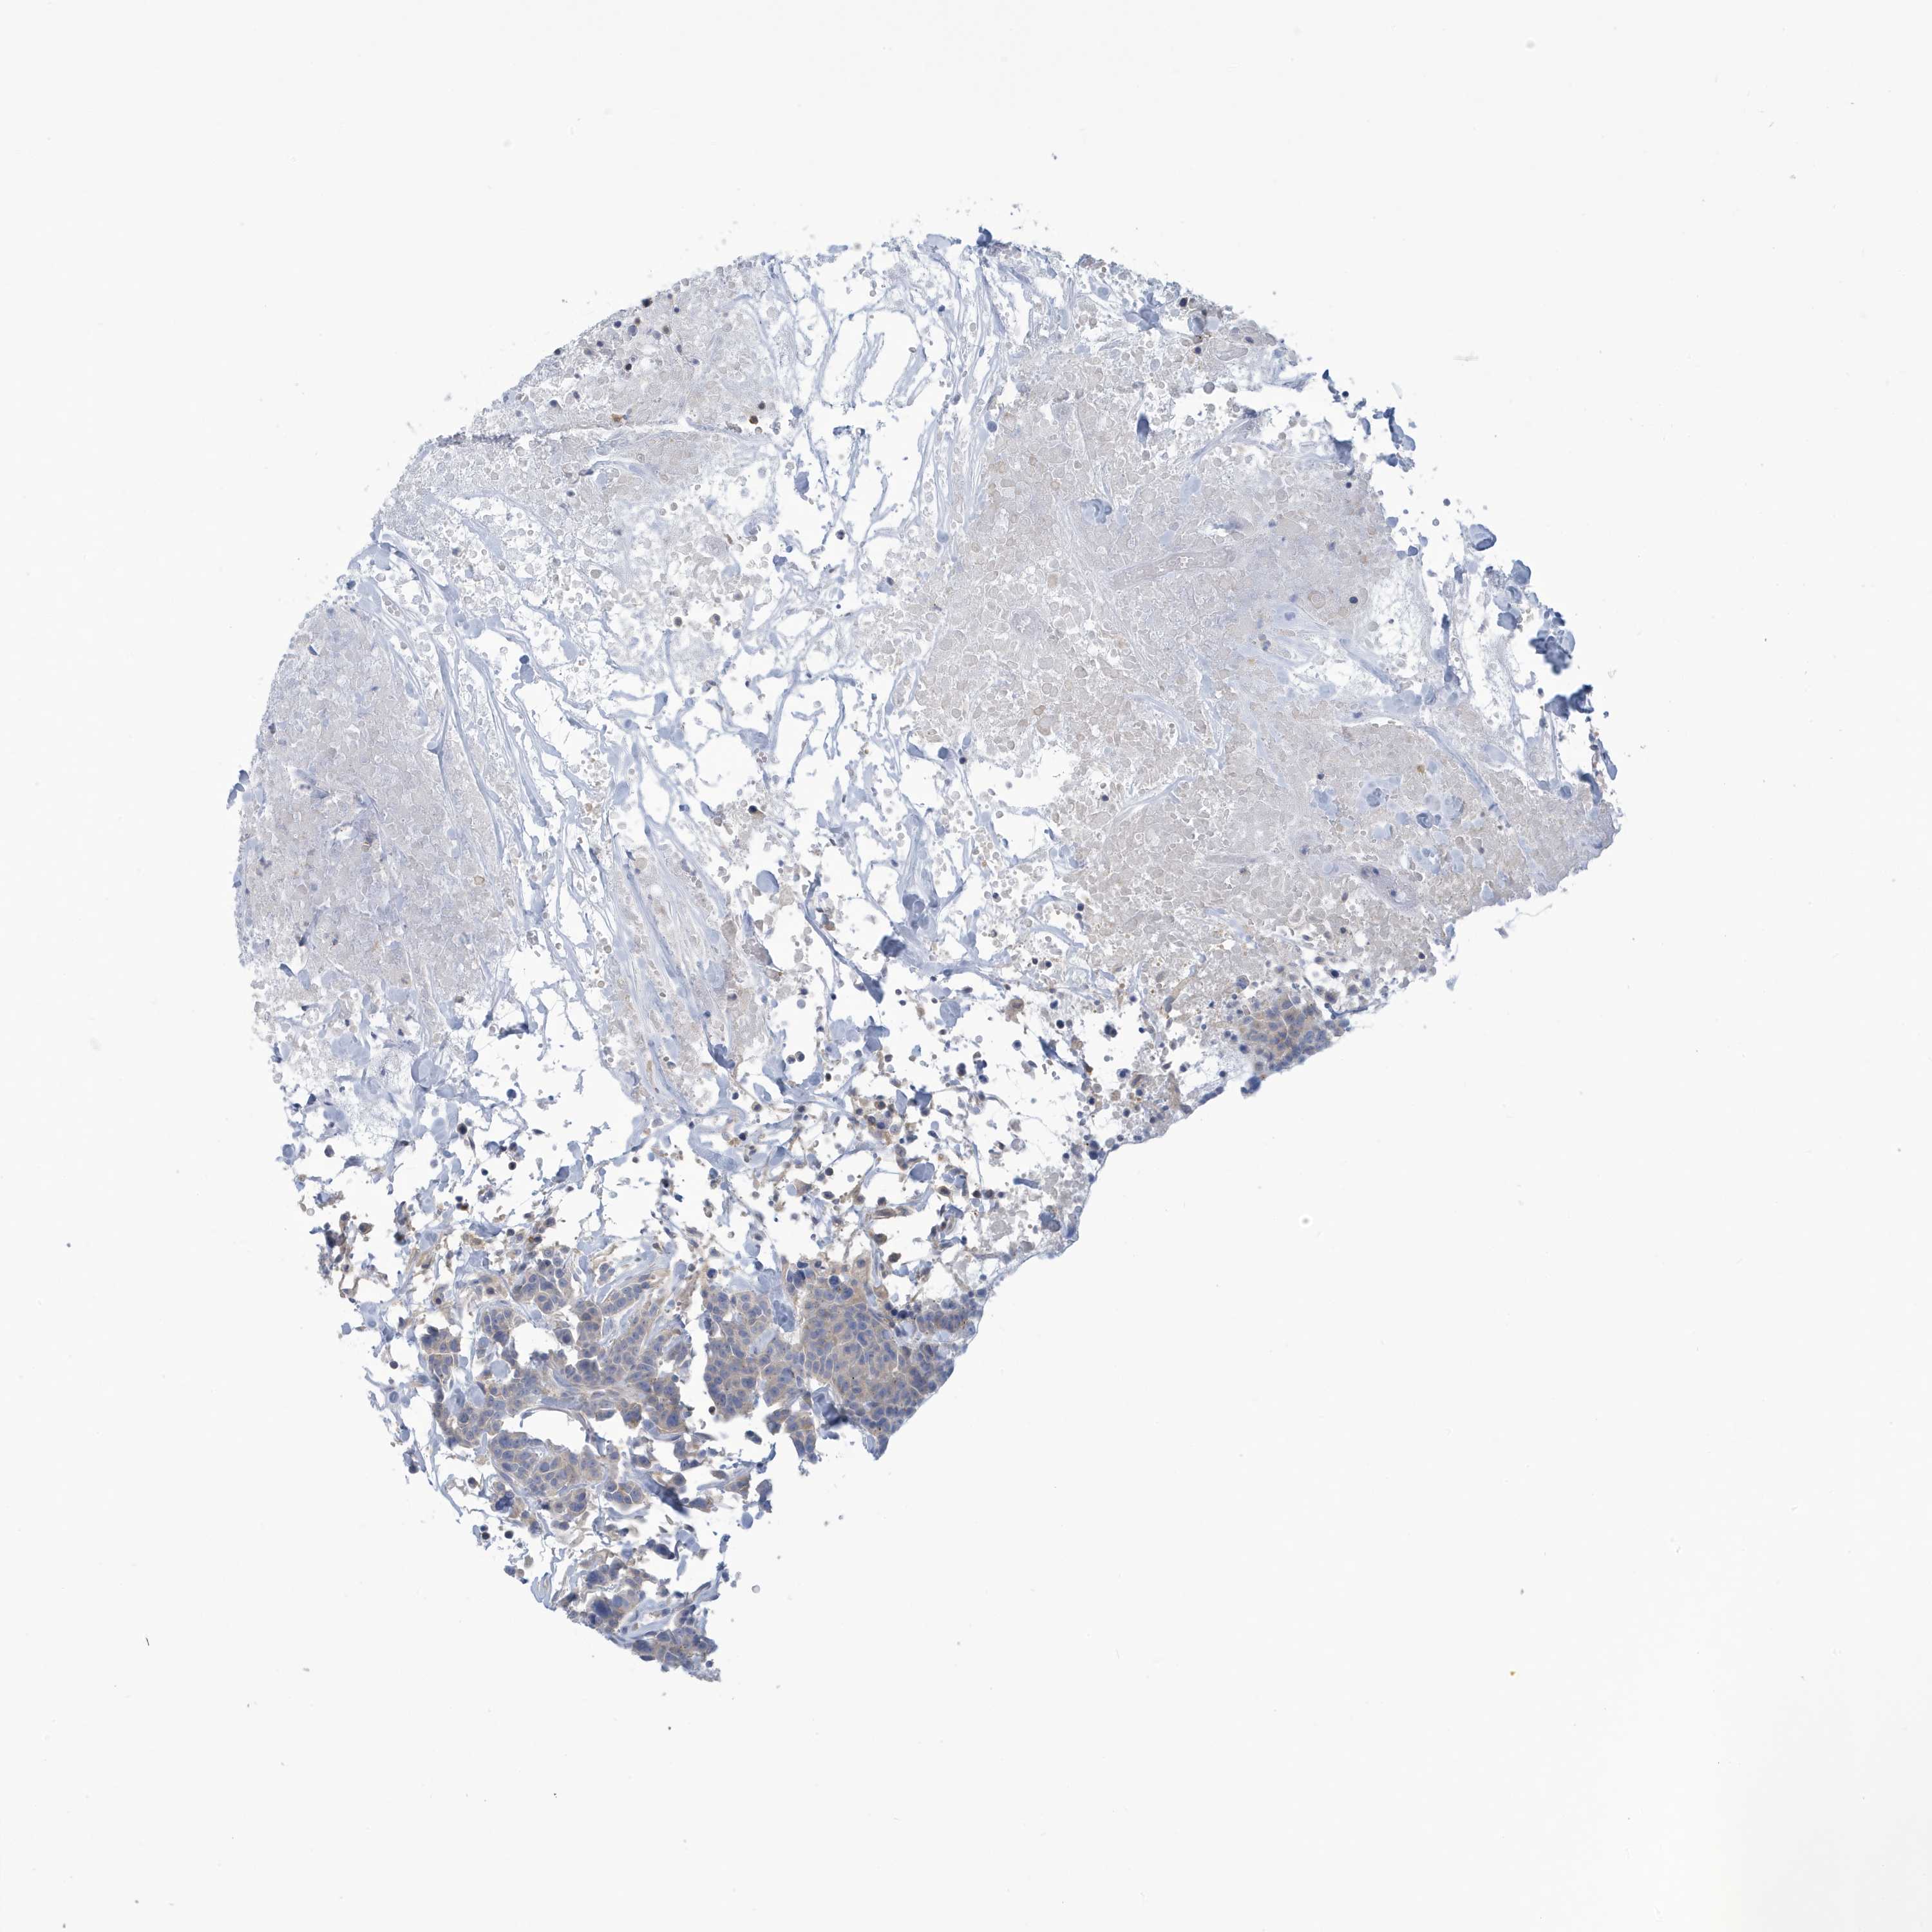

BRCA TCGA BRCA VALIDATION PROTEIN EXPRESSION

ANTIBODIES

AND

VALIDATION